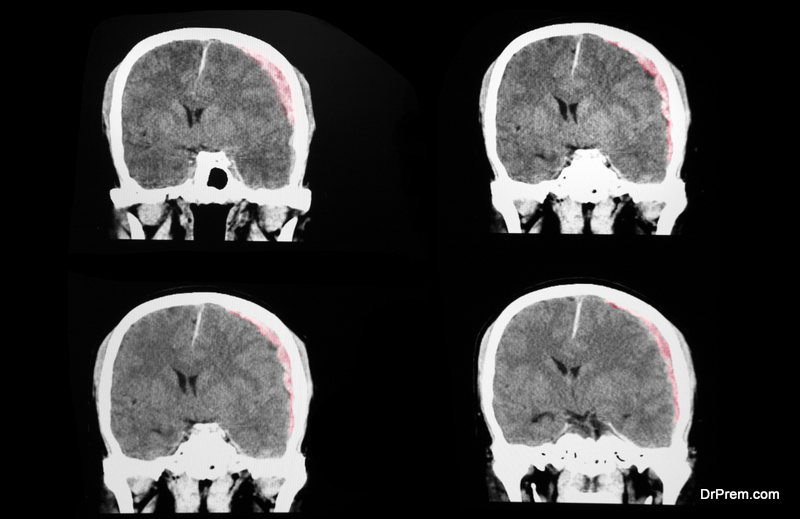

Cerebral Edema Images Best Treatment For Cerebral Edema Osmotherapy is one of the mainstays of treatment for cerebral oedema, aimed at reducing brain swelling by drawing fluid out of the brain tissue. Causes include brain injuries, infections and. Minor cases of brain swelling due to causes such as moderate altitude sickness or a. Prevent further injury from the cerebral edema and remediate the original insult causing the cerebral. Best Treatment For Cerebral Edema.